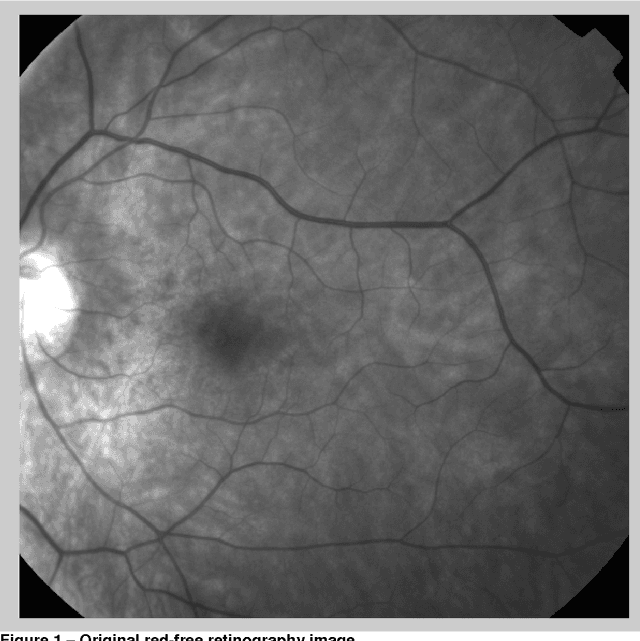

Blueworks - Medical Expert Diagnosis is developing an application, BWEye, to be used as an ophthalmology consultation decision support system. The implementation of this application involves several different tasks and one of them is the implementation of an ophthalmology images registration algorithm. The work reported in this document is related with the implementation of an algorithm to register images of angiography, colour retinography and redfree retinography. The implementations described were developed in the software MATLAB. The implemented algorithm is based in the detection of the bifurcation points (y-features) of the vascular structures of the retina that usually are visible in the referred type of images. There are proposed two approaches to establish an initial set of features correspondences. The first approach is based in the maximization of the mutual information of the bifurcation regions of the features of images. The second approach is based in the characterization of each bifurcation point and in the minimization of the Euclidean distance between the descriptions of the features of the images in the descriptors space. The final set of the matching features for a pair of images is defined through the application of the RANSAC algorithm. Although, it was not achieved the implementation of a full functional algorithm, there were made several analysis that can be important to future improvement of the current implementation.